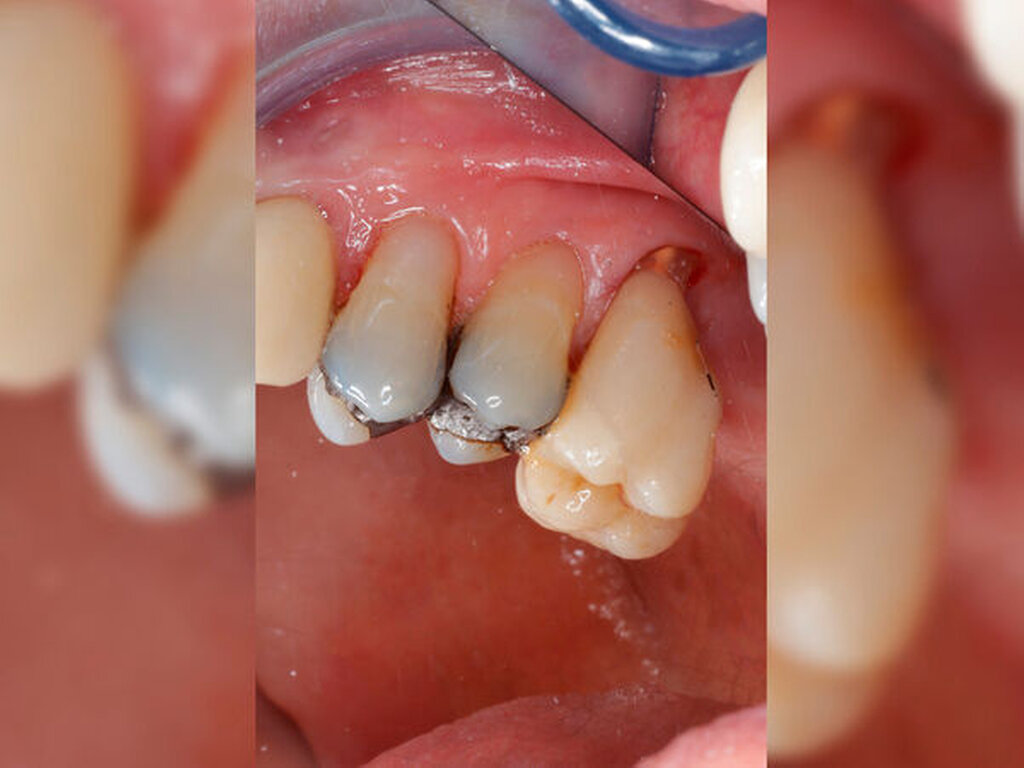

Ein 59-jähriger Patient stellte sich erstmals 2015 mit rezidivierenden pochenden Beschwerden und zeitweise zusätzlich auftretendem Pusaustritt an Zahn 16 vor. Klinisch zeigte sich ein ausgeprägter Attachmentverlust distal mit bis apikal sondierbarer distobukkaler Wurzel, Furkationsbeteiligung und Pusaustritt sowohl über den Parodontalspalt als auch durch einen distobukkal gelegenen Fistelausgang. Zunächst erfolgte die endodontische Behandlung des Zahnes 16 mit anschließender systematischer PA-Therapie. Bei persistierender parodontaler Problematik an 16 wurde die Möglichkeit der Teilamputation der distobukkalen Wurzel mit dem Patienten diskutiert, um die Hygienefähigkeit und damit die Prognose des Zahnes zu verbessern. Auch über die Extraktion als Alternative wurde der Patient aufgeklärt. Er war allerdings motiviert, seinen Zahn so lange wie möglich zu erhalten.

So erfolgte die Amputation der distobukkalen Wurzel mit anschließender Versorgung des Zahnes mittels Vollkrone. Die Situation an 16 ist seitdem für den Patienten subjektiv stabil, die aktuelle Röntgenkontrolle zeigt jedoch eine Progredienz der parodontalen Defekte trotz regelmäßiger UPT und subjektiv guter Mitarbeit des Patienten, was die Prognose des Zahnes negativ beeinflusst. Ursächlich hierfür kann eine persistierende parodontale Infektion durch den trotz Wurzelamputation immer noch schwer für die häusliche Mundhygiene zugänglichen Furkationsbereich mit enger Lagebeziehung der mesiobukkalen und der palatinalen Wurzel sein. Der Patient ist allerdings aktuell mit der Situation zufrieden und beschwerdefrei und wünscht daher noch keine Extraktion des Zahnes, auch wenn diese sich nun fünf Jahre nach dem initialen Befund nicht mehr sehr lange vermeiden lassen wird.